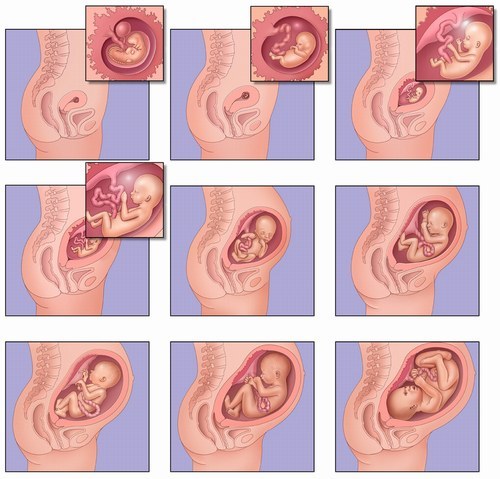

Durante la 15° Settimana di gravidanza e nel secondo trimestre, molte donne tendono a rilassarsi un po’ di più. Molti dei peggiori sintomi della gravidanza, come nausee mattutine, stanchezza diminuiscono sempre più man mano che i giorni passano. Il dolore che giunge alla fine della gravidanza è lontano, quindi puoi finalmente rilassarti e goderti la gravidanza.

Come menzionato in precedenza, la 15° Settimana di gravidanza non porta cambi significativi nel corpo. Molte donne guadagnano circa 5 libbre durante la settimana, sebbene l’aumento del peso vari da mamma a mamma. E’ abbastanza naturale se hai guadagnato un po’ di più per quanto riguarda il peso. La situazione più difficile da affrontare in questo periodo è che i legamenti che supportano l’utero stanno continuando a crescere, causando fitte nell’addome.

Dal momento che il tuo ombelico non sta ancora spuntando e non hai guadagnato peso a sufficienza, non hai ancora dovuto imparare a camminare in una posizione, così per te tutto è nuovo e devi abituarti a dormire su un lato, come sedere e come stare in piedi con la giusta postura. Se fai pratica sin da ora, sarà molto più facile andando avanti con la gravidanza, in cui dovrai cercare di alleviare il dolore.